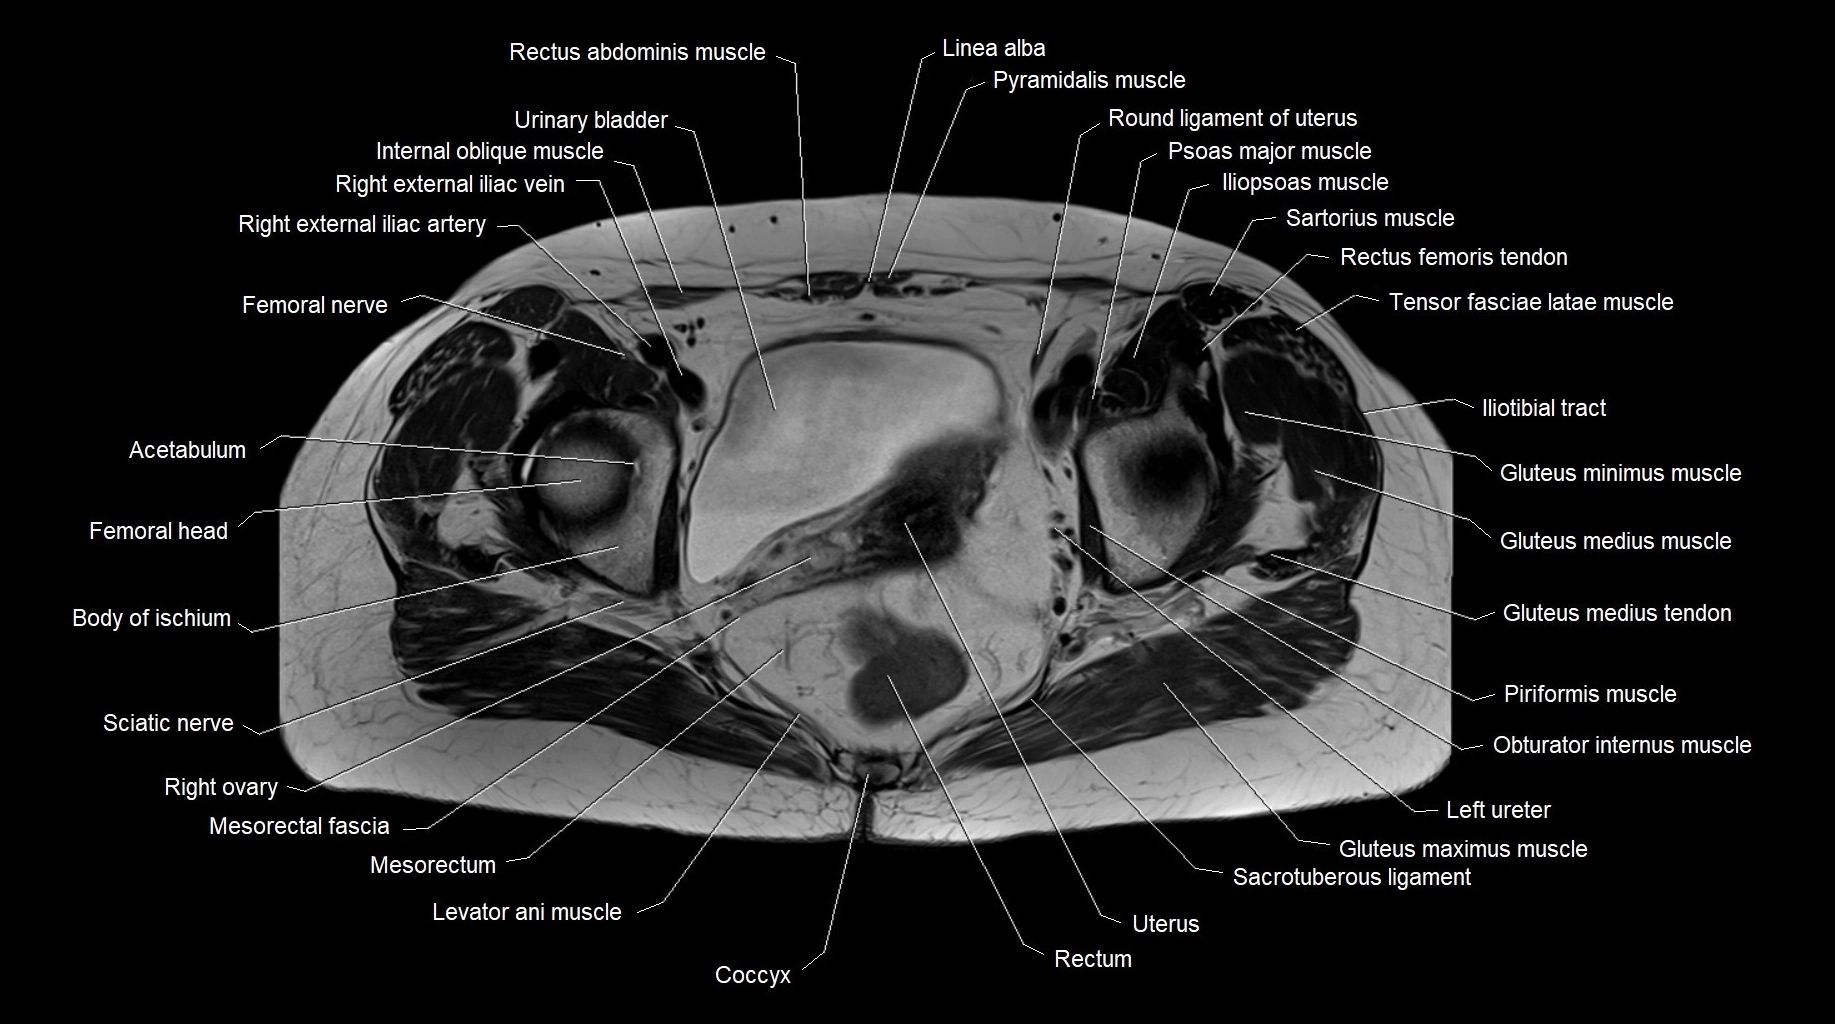

MRI images